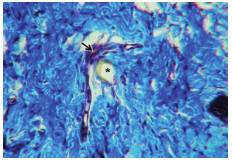

The head, mouthparts and the probing process of R. prolixus are shown in figure 1. Triatomines are regarded to be vessel-feeders because they obtain blood from vertebrate hosts by directly inserting their mouthparts into vessels (solenophagy or capillary feeding) (9). Triatomines rely on the sense of CO2 to search for blood meals from sleeping hosts (13). Contact with the host occurs only during feeding, which lasts approximately 20 to 30 min (14). It has been described that these insects feed on a host swinging their proboscis forward and piercing the skin by rapid alternating movements of the resistant mandibles which penetrate only into the superficial tissues. Then, the maxillae (maxillary bundle) penetrate deeply into the dermis with restless twisting movements (9).

Triatomines possess a wide variety of bioactive molecules in the saliva which facilitate the blood meal by reducing host physiological responses related to haemostasis, inflammation, and immune activation. In R. prolixus, saliva deposition into the host skin occurs throughout the probing and engorgement phases of the feeding (12,14). Feeding takes place from blood vessels rather than from small hemorrhages which are formed as a result of probing. When the maxillary bundle enters a blood vessel of suitable caliber, probing ceases and the insect gut begins to engorge (9). Blood ingestion through the food canal is aided by the cibarial pump, which is regulated by several strong muscles of the insect head (7). The bug continues to suck up its blood meal until it is full, but the feeding process is not always continuous and may be interrupted and repeated (9).

Third- and fourth-instar uninfected nymphs of R. prolixus were obtained from the insectary colonies of the Departamento de Microbiología of the Facultad de Salud of Universidad del Valle in Cali, Colombia. In the Laboratorio de Histología of the University, an anesthetized laboratory mouse (Mus musculus) was exposed to the triatomines for blood-feeding (figure 2 and figure 3). Triatomines were decapitated with a curved iris scissor during blood-feeding. We obtained biopsy samples of the skin pierced by the feeding apparatus or proboscis, and of the head of the insect, and processed them accordingly.

Light microscopy (figure 4 and figure 5) was performed in the Laboratorio de Ingeniería de Materiales of Universidad del Valle and scanning electron microscopy procedures (JEOL microscope JSM6490LV) (figure 6, figure 7 and figure 8) were performed in the Laboratorio de Materiales de la Facultad de Ingeniería of Universidad del Valle. Animal experimentation was part of the practical component of the subjects "Basic histochemical techniques" and "Electron microscopy techniques" taken by one of the authors.